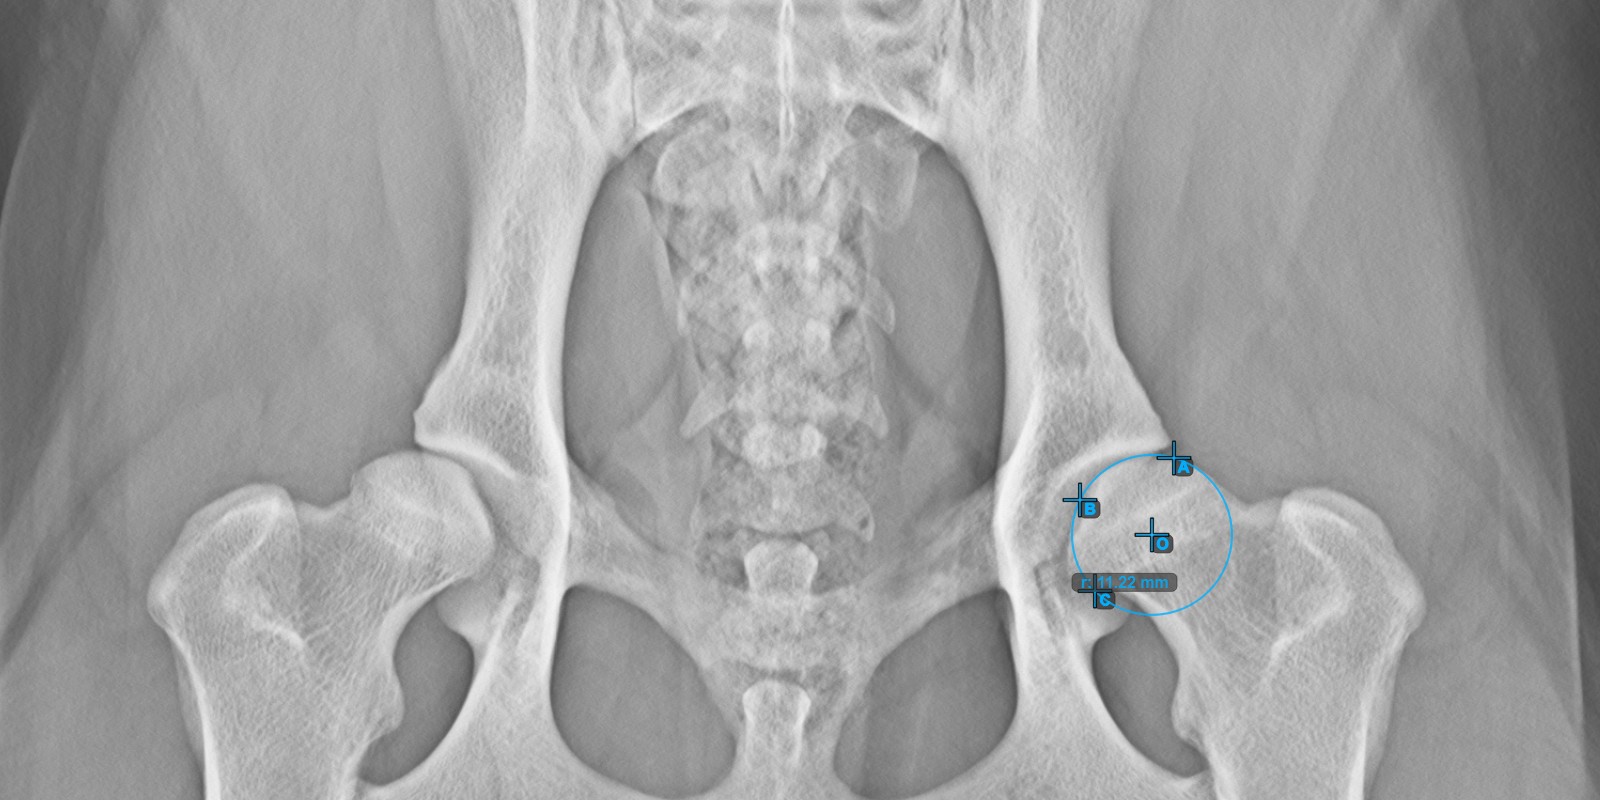

Das untenstehende Bild zeigt die typische Platzierung der drei Punkte auf der Gelenkfläche des rechten Caput Femoris.

Mark the three points on the articular surface of the right Caput Femoris (outside of the Fovea Capitilis). Regardless of the order, make sure to mark the most cranial point, the most caudal point and the midpoint of the femoral head. A circle will be automatically constructed based on the three placed poin